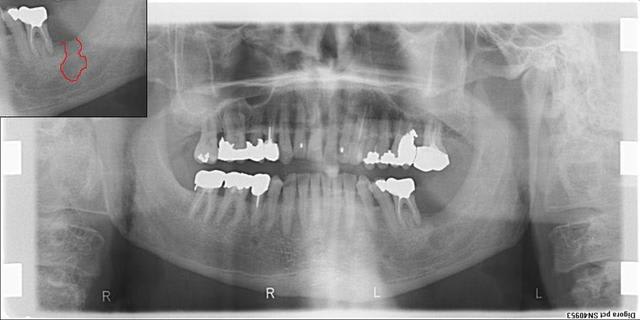

La pano....

...la voilà.

Pas de chance ! C'est le seul endroit où il n'y a pas de débordement d'amalgame !

Il n'y aurait pas une lésion osseuse juste sous ces bourgeons???

S'il y a une image radio, elle est où ?